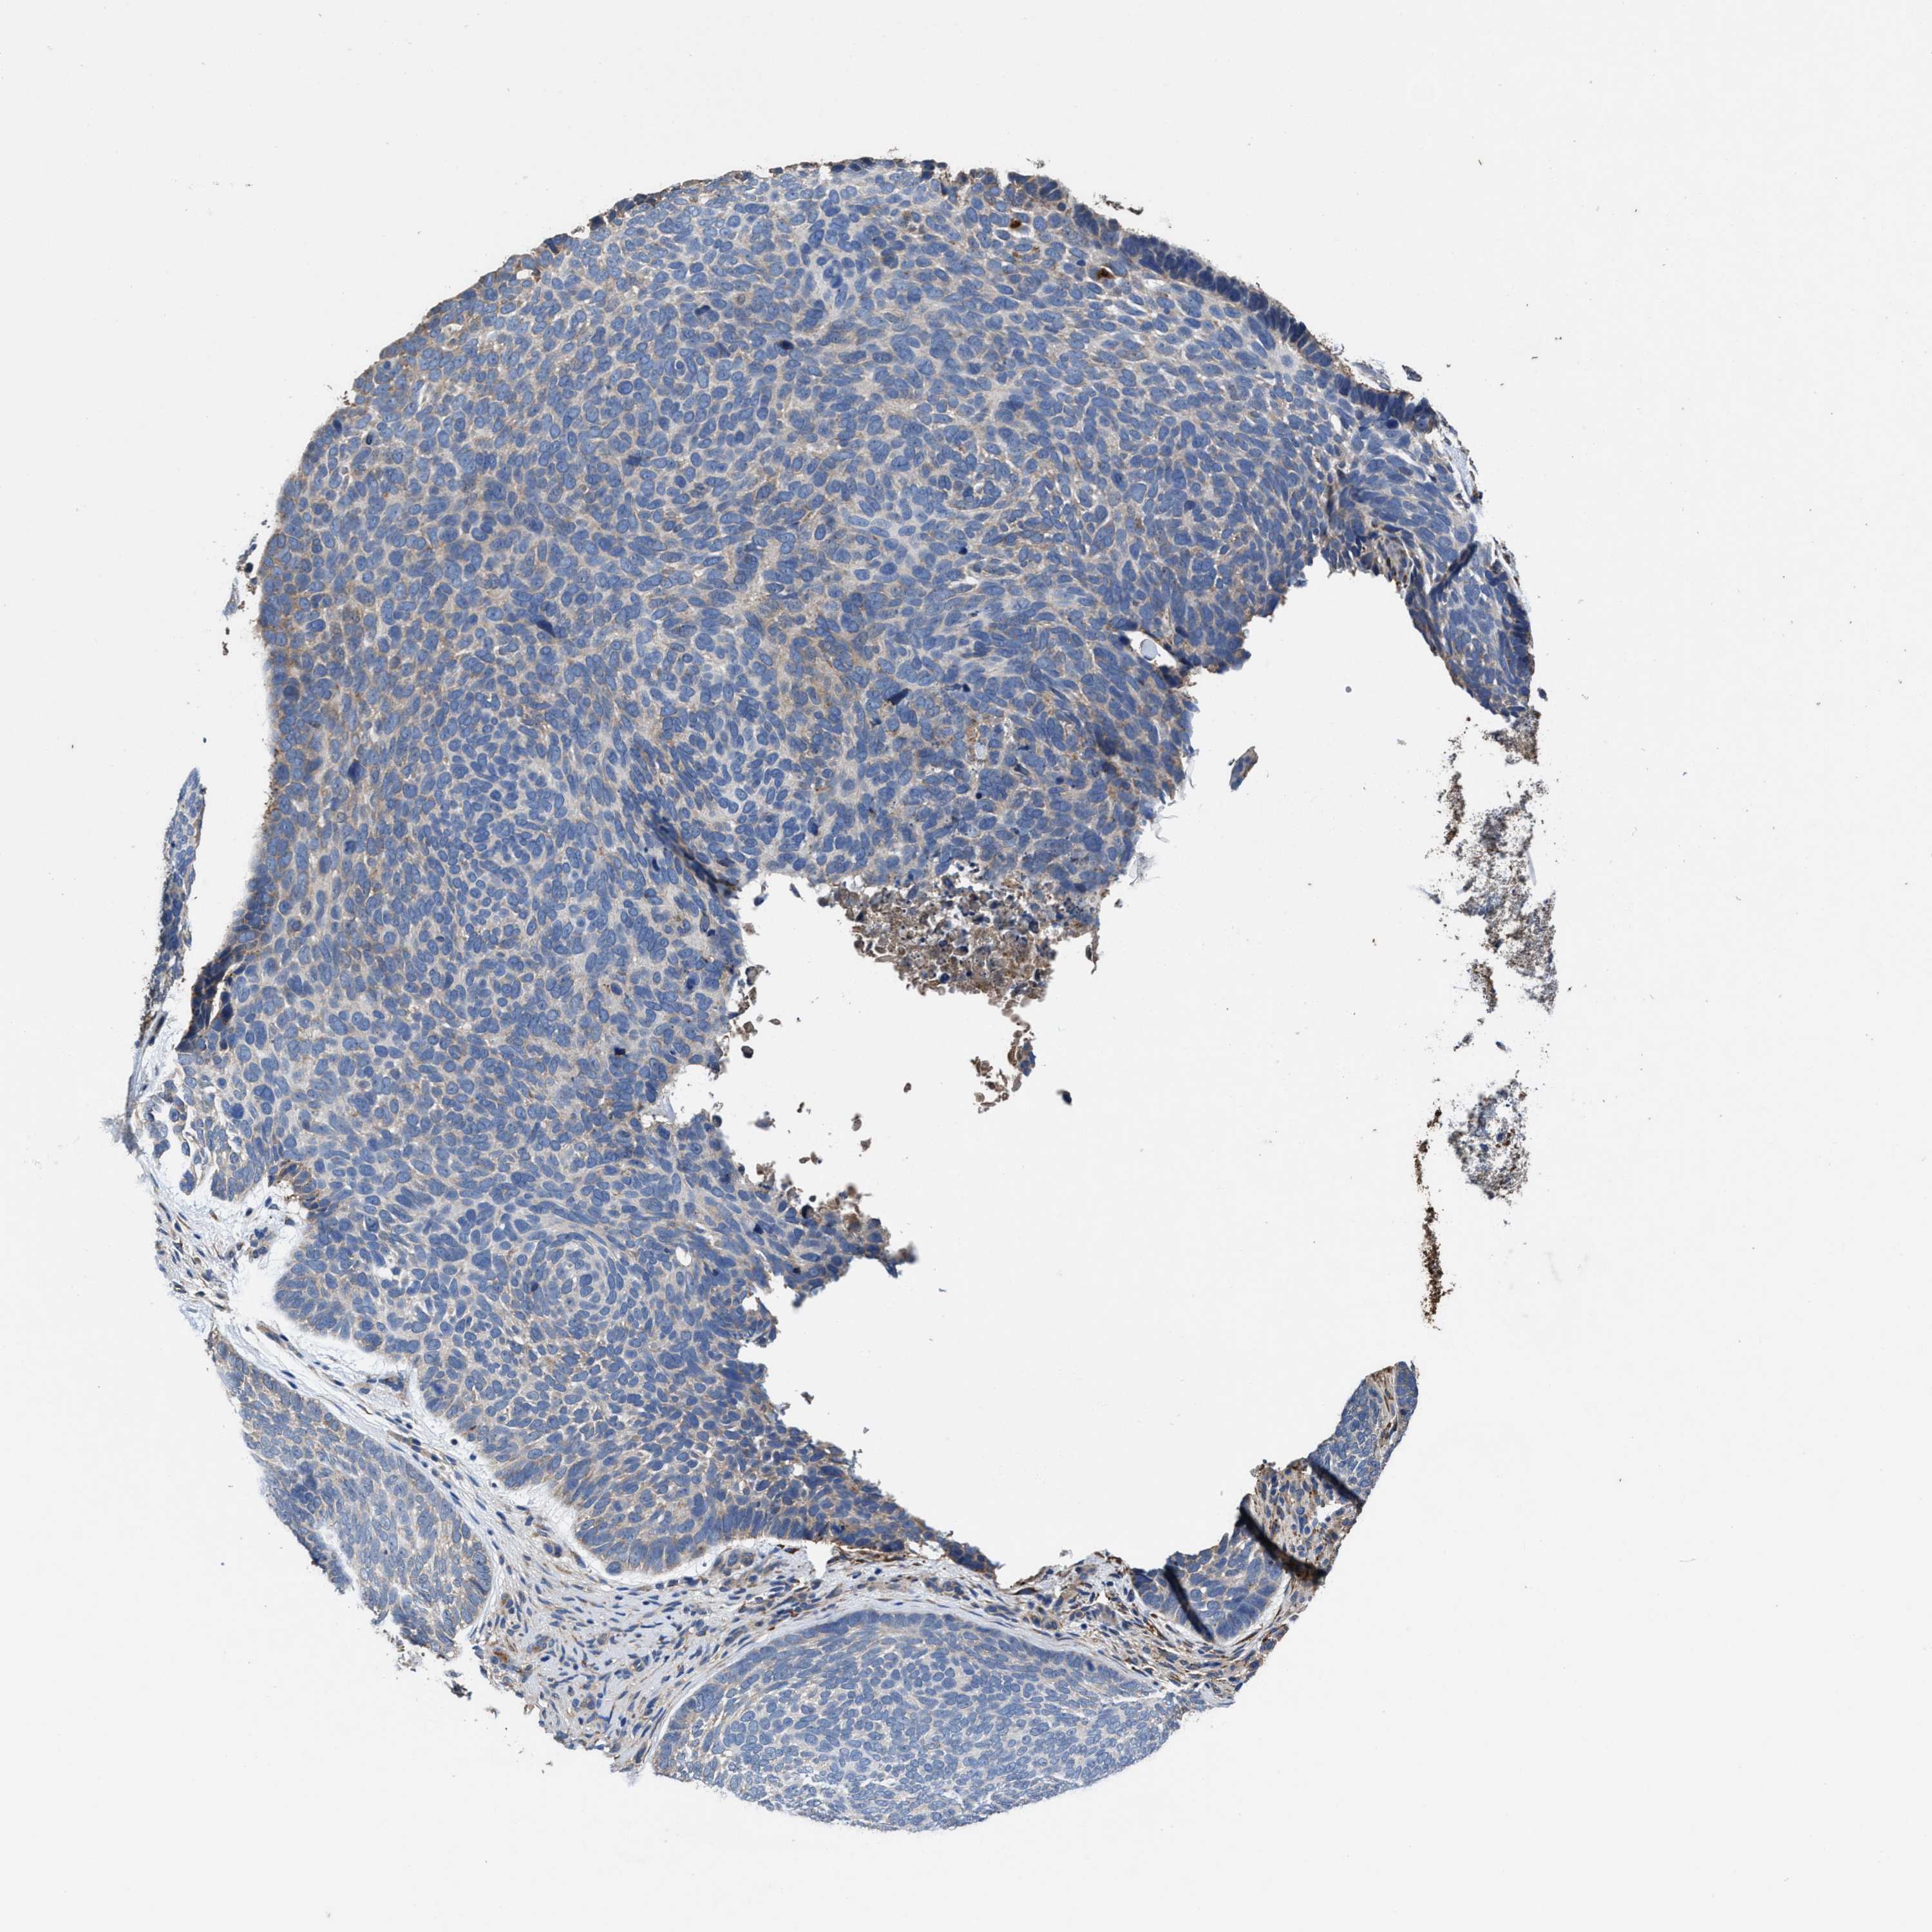

SKIN CANCER - Protein expressioni

A mouse-over function shows sample information and annotation data. Click on an image to view it in a full screen mode. Samples can be filtered based on level of antibody staining by selecting one or several of the following categories: high, medium, low and not detected. The assay and annotation is described here.

Antibody stainingi

Antibody staining in the annotated cell types in the current human tissue is reported as not detected, low, medium, or high, based on conventional immunohistochemistry profiling in selected tissues. This score is based on the combination of the staining intensity and fraction of stained cells.

Each image is clickable and will lead to virtual microscopy that enables deeper exploration of all samples and also displays staining intensity scores, fraction scores and subcellular localization as well as patient and tissue information for each sample.

Antibody HPA020378

Staining

High

Medium

Low

Not detected

Intensity

Strong

Moderate

Weak

Negative

Quantity

>75%

75%-25%

<25%

None

Location

Nuclear

Cytoplasmic/membranous

Cytoplasmic/membranous,nuclear

Basal cell carcinoma